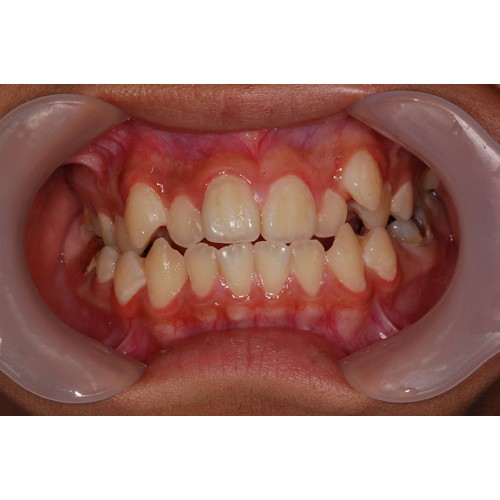

CHUNCHU'S ORTHODONTIC CLINIC# BEFORE_AFTER

춘추치과교정과를 방문해주신 분들의전후 사진을 확인해보세요.